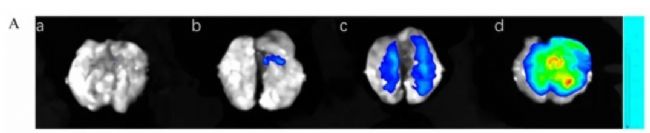

利用Clinx勤翔IVScope 8200小動(dòng)物活體成像系統(tǒng),以DiR熒光探針標(biāo)記FA-PPI-Ms(葉酸修飾的重樓皂苷 I 負(fù)載三七多糖膠束),在膠原誘導(dǎo)關(guān)節(jié)炎(CIA)大鼠模型中,追蹤納米制劑的體內(nèi)分布與關(guān)節(jié)靶向性。

成像結(jié)果:

FA-PPI-Ms靜脈注射后在關(guān)節(jié)炎癥部位特異性富集,熒光信號(hào)強(qiáng)度顯著高于游離 DiR組和非靶向膠束組,且持續(xù)至72小時(shí),證實(shí)其通過FA受體介導(dǎo)的主動(dòng)靶向結(jié)合活化巨噬細(xì)胞。結(jié)合關(guān)節(jié)腫脹評(píng)分、micro-CT及組織學(xué)分析,F(xiàn)A-PPI-Ms通過抑制 JAK2-STAT3通路促進(jìn) M1巨噬細(xì)胞向M2極化,顯著減輕關(guān)節(jié)炎癥與骨侵蝕,且對(duì)心、肝、脾、肺、腎無明顯毒性。